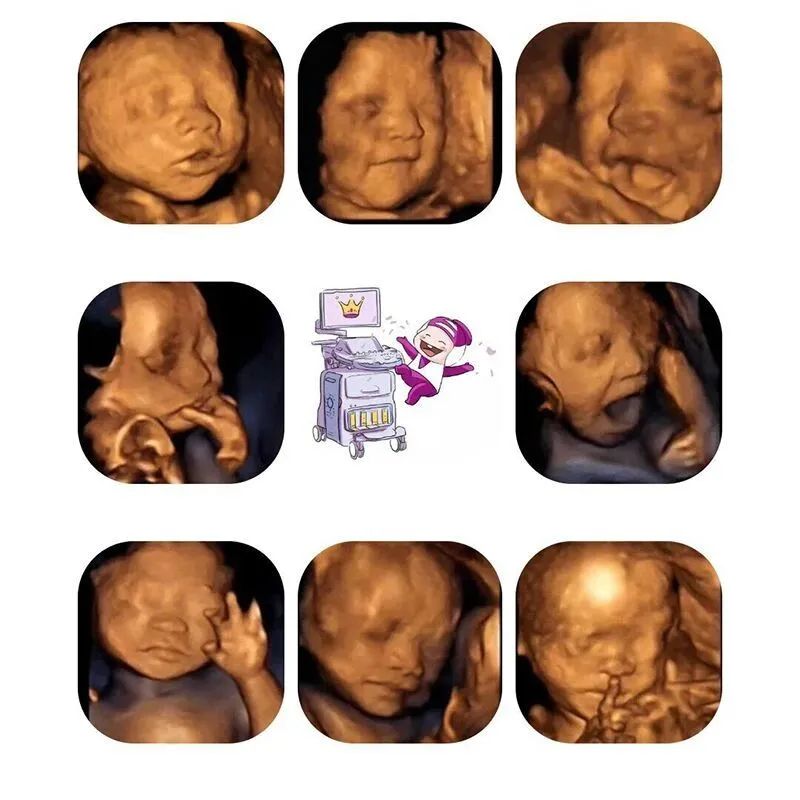

你瞧,小不点在那儿噘嘴、啃手指、打哈欠、扮鬼脸,就算对着肚皮拳打脚踢“干坏事”,都能萌化老母亲的心~

查看胎宝宝的活动:可以检查到胎宝宝在宫内是否缺氧,肢体运动、胎儿的吞咽动作等,能够很好地看到胎儿在孕妈妈体内的活动状况,说不定还可能看见宝宝做鬼脸、伸舌头哦。

胎宝宝是否畸形:四维彩超检查是发现胎儿畸形的个重要手段。通常孕妈妈在妊娠22-28周做四维彩超筛查胎儿畸形,因为这个时段胎儿的各个器官都已经发育成型,比较容易看出有没有畸形。